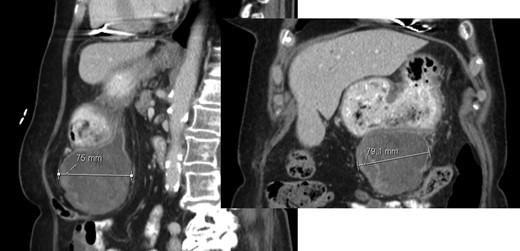

A 40-year-old woman with past medical history of c-section at the age of 26, was referred to our Hepatobiliary Unit in 2013, with diagnose of liver tumor with 16.6 cm (Fig. 2) suggestive of solitary fibrous tumor.

Abdominal Magnetic Resonance – heterogeneous liver mass in segment 4 with 16.6 cm.

No distant metastasis was identified.